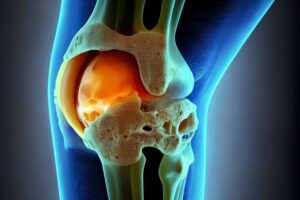

Auf unserer Seite finden Sie umfangreiche Informationen zu orthopädischen Beschwerden und Erkrankungen. Von der Arthrose über Bandscheibenvorfälle bis hin zu Kreuzbandriss und weiteren Sportverletzungen: wir geben Ihnen einen Überblick über die häufigsten orthopädischen Krankheitsbilder, wie sie behandelt werden können und inwieweit ein Bildgebungsverfahren, wie eine (z.B. MRT Knie, Rücken MRT) bei der Diagnose bei der Diagnose unterstützend wirken können.

Unsere Liste zu den häufigsten orthopädischen Problemen ist alphabetisch von A-Z geordnet. So finden Sie schnell und unkompliziert den Beitrag, der Ihnen weiterhilft. Von Krankheiten, über Verletzungen bis hin zu schmerzhaften Zuständen wie Arthrose, Meniskusschaden und Schleimbeutelentzündung – hier finden Sie die wichtigsten Informationen.